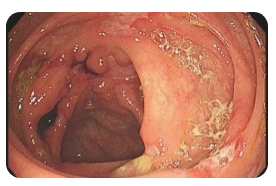

🧫 왼쪽 옆구리 통증 신장

신장은 체내 노폐물을 걸러주는 중요한 기관으로, 이상이 생기면 왼쪽 옆구리 통증을 유발할 수 있습니다. 요로결석의 경우에는 갑작스럽고 심한 통증이 나타나며, 신우신염은 감염으로 인해 열과 함께 통증이 동반됩니다. 신장 결석은 통증이 소변 볼 때 심해지는 특징이 있고, 경우에 따라 혈뇨가 나타나기도 합니다. 통증이 심하거나 발열이 함께 있다면 반드시 병원 진료를 받아야 합니다.